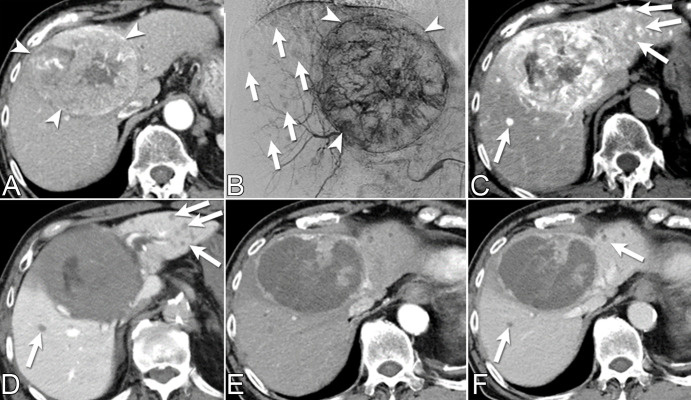

Figure 2:

Multiple incidental small hepatocellular carcinomas (HCCs) detected with CT during hepatic arteriography (CTHA) and CT arterial portography (CTAP) during transarterial chemoembolization (TACE) for a patient presenting with a recurrent HCC. (A) Diagnostic quadriphasic contrast-enhanced CT performed 3 weeks before TACE shows solitary large central HCC (arrowheads). (B) Pre-TACE digital subtraction angiographic image from the common hepatic artery shows large hypervascular tumor (arrowheads) and small hypervascular nodules of unclear clinical significance (arrows). (C, D) CTHA and CTAP demonstrate multiple small hypervascular tumors with portal venous washout (arrows), compatible with incidental HCCs. (E, F) One month post-TACE follow-up contrast-enhanced CT arterial phase and portal venous phase scans help confirm treated large HCC and satellite hypovascular nodules (arrows in F). The ability to obtain arterial and portovenous images with combined angio-CT systems allows prompt differentiation between true HCCs and other regenerative and dysplastic liver nodules.